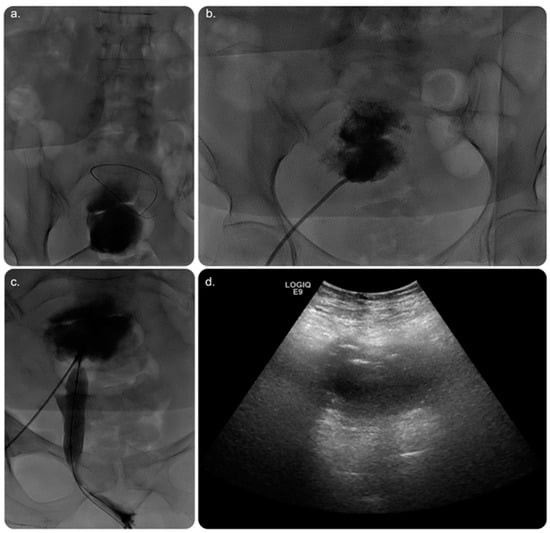

CT of the abdomen and pelvis with intravenous (IV) contrast revealed a sizable endometrial cavity collection with air foci, faint fluid–fluid levelling, and irregular endometrial enhancement. Moreover, an enhanced cervical lesion was identified (Figure 1). Her laboratory results indicated a slight increase in white blood cell count; however, other test results were within the normal range. Pap smear and human papillomavirus tests indicated no evidence of malignancy.

Figure 1. Reformatted computed tomography (CT) images of the abdomen and pelvis with (intravenous) IV contrast. (a) Axial cut CT of the pelvis showing an endometrial fluid collection with air focus at the non-dependent part of the endometrium. The endometrial lining shows an evident contrast enhancement. No CT evidence of anterior abdominal scar is seen, proving no prior history of Caesarean birth. (b) Coronal and (c) sagittal CT of the abdomen and pelvis showing endometrial fluid collection with an air focus at the non-dependent part of the endometrium.

It is performed using ultrasound, fluoroscopy, and/or cross-sectional imaging guidance. Ultrasound guidance is the preferred modality, wherein CT is implemented in cases with deep collections, difficult access, or lesions that cannot be visualised using an ultrasound scan [2] (Figure 1 and Figure 2).